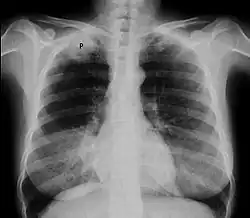

Chest X-ray showing a Pancoast tumor (labeled as P, non-small cell lung carcinoma, right lung), from a 47-year-old female smoker.

Diagnosis of a Pancoast tumor can be difficult in the early stages to the similarity of its symptoms with other conditions such as arthritis, with shoulder pain being one of the only symptoms that might indicate further imaging for a patient.[14] Though a chest x-ray is a good screening test and might be the first mode of imaging used, they are not easily seen during the early stages of the disease due to their size and location in the chest.[15]